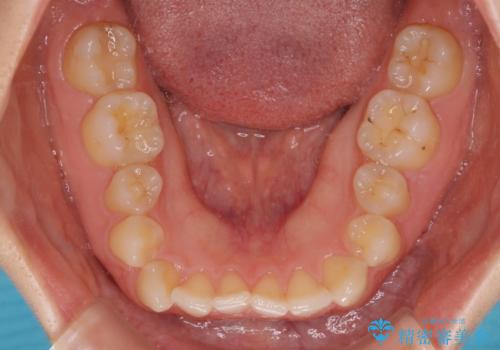

- 前歯の隙間やクロスバイトを気にして来院された患者様です。

結婚式の予定があり、可能であれば結婚式までに治療を終えたいとのことで、短期間で治療をおける可能性の高いワイヤー装置にて矯正治療を行うこととしました。

ギリギリとなりましたが、結婚式直前にワイヤー装置を外すことができました。

ワイヤー装置除去後に細かい部分を短期間のマウスピース矯正にて仕上げました。